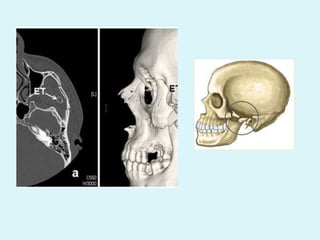

TRIPOD #

 Fractures of zygoma/ Tripod

#

 2nd most commonly injured

 Direct trauma

 Lower segment of zygoma

pushed medially and

posteriorly – leading to

flattening of malar

prominence and step-

deformity

 Clinical features

 Flattening, step deformity

 Anaesthesia of infraorbital nerve

area

 Trismus

 Obliquity of palperal fissure

 Restricted EOM

 Periorbital emphysema

 Diagnosis- CT, Water’s &

exaggerated Water’s

 Treatment

 ORIF